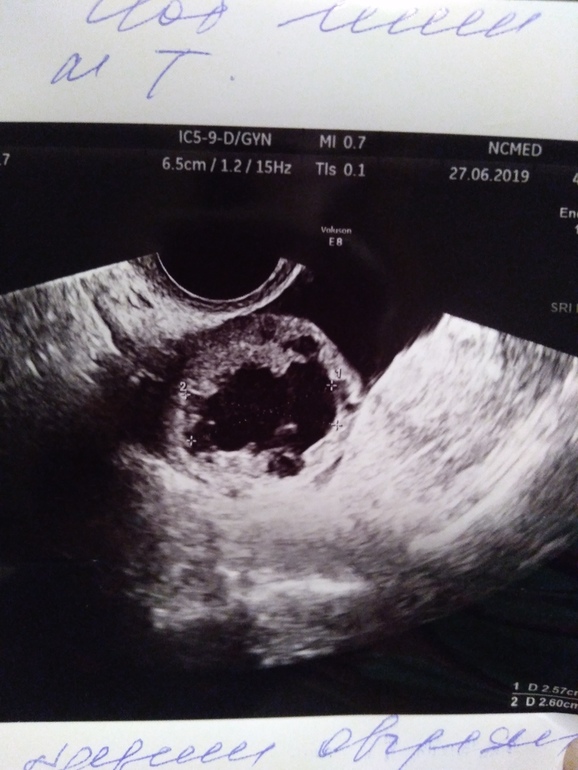

Се6одня на узи эндометрий 13 мм

Жт справа 25,6х25 мм. При цдк обильная васкуляризация

Свободная жидкость в умеренном количестве.